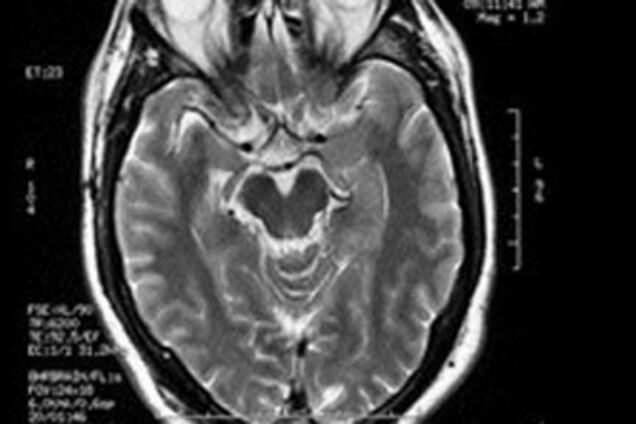

Для этого специалисты много лет изучали мозг людей с высоким уровнем интеллекта и выяснили, что в зоне мозга, отвечающей за восприятие зрительной и чувственной информации, у них содержится высокая концентрация так называемых молекул NAA. Эти молекулы ответственны за интеллект и творческое мышление.

Исследователи смогли описать и механизм гениальности. Молекулы NAA содержатся в тканях серого вещества головного мозга, которое состоит из нейронов. Связь между ними происходит посредством аксонов, являющихся частью белого вещества. При этом у среднестатистических людей аксоны покрыты толстой жировой оболочкой, которая позволяет нервным импульсам двигаться быстрее. У интеллектуалов же жировая оболочка крайне тонка, за счет чего продвижение импульсов происходит очень медленно. Это, в свою очередь, влияет на скорость мышления человека. В соответствии с описанным механизмом высокоинтеллектуальные люди думают намного медленнее остальных. Однако в результате длительных размышлений способны найти поистине гениальное решение.